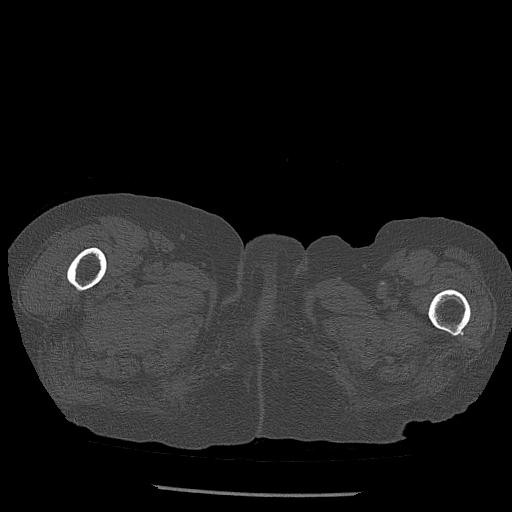

56476 8/28 4R 1/21 2R 左足関節 デジカメ写真 72歳女性 右足関節AS